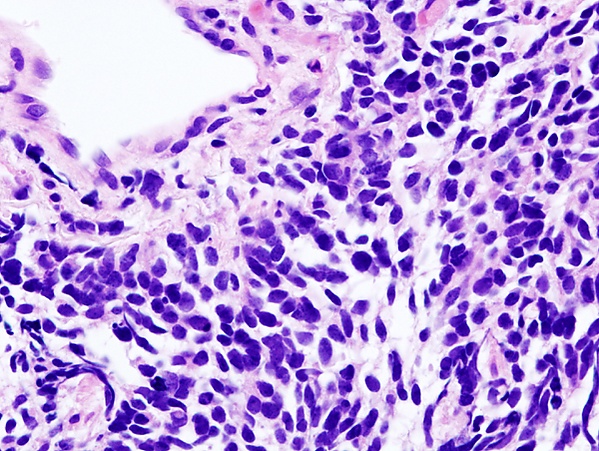

Гистологическая характеристика рака лёгкого достаточно условна, поскольку клиническое течение может сильно различаться даже для опухолей с одинаковой структурой. Медленнее всего растёт дифференцированный плоскоклеточный рак; для недифференцированного рака характерно быстрое течение с обширным метастазированием. Мелкоклеточный рак лёгкого принадлежит к числу самых злокачественных опухолей. Он отличается коротким анамнезом, скрытым и быстрым протеканием, ранним метастазированием, плохим прогнозом.